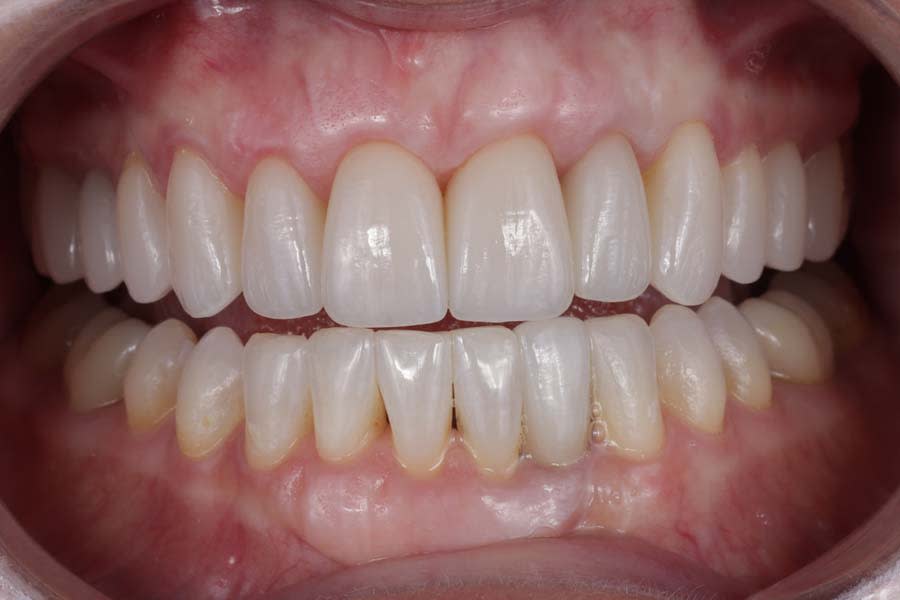

Post-treatment photographs demonstrating the successful outcome of the case are shown in Figure 15 through Figure 19.

Clear aligners (Invisalign) were used to correct gingival margin discrepancies, reduce the black triangle between teeth Nos. 9 and 10, and optimize occlusal forces by uprighting posterior teeth. This orthodontic phase, paired with airway considerations, enabled functional and esthetic improvements without compromising tongue space. Establishing adapted centric posture via deprogramming created a stable occlusal scheme, thereby minimizing risks of further attrition or restoration failure. Lithium-disilicate crowns and resin infiltration restored function and delivered a natural, esthetic smile, with precise laboratory collaboration ensuring accurate shade and contour.

This case exemplifies the transformative potential of a structured, systematic approach in transitioning a patient from single-tooth dentistry to comprehensive care. By addressing biomechanical, functional, periodontal, and dentofacial risks through integrated orthodontic and restorative treatments, the treatment achieved a stable, functional occlusion and an esthetically pleasing smile. The use of clear aligners, precise occlusal management, and cohesive restorations resolved immediate concerns and reduced long-term risks. Since treatment completion in early 2023, the stability of the restorations and the patient’s satisfaction have underscored the success of this approach in delivering lasting functional and esthetic outcomes.